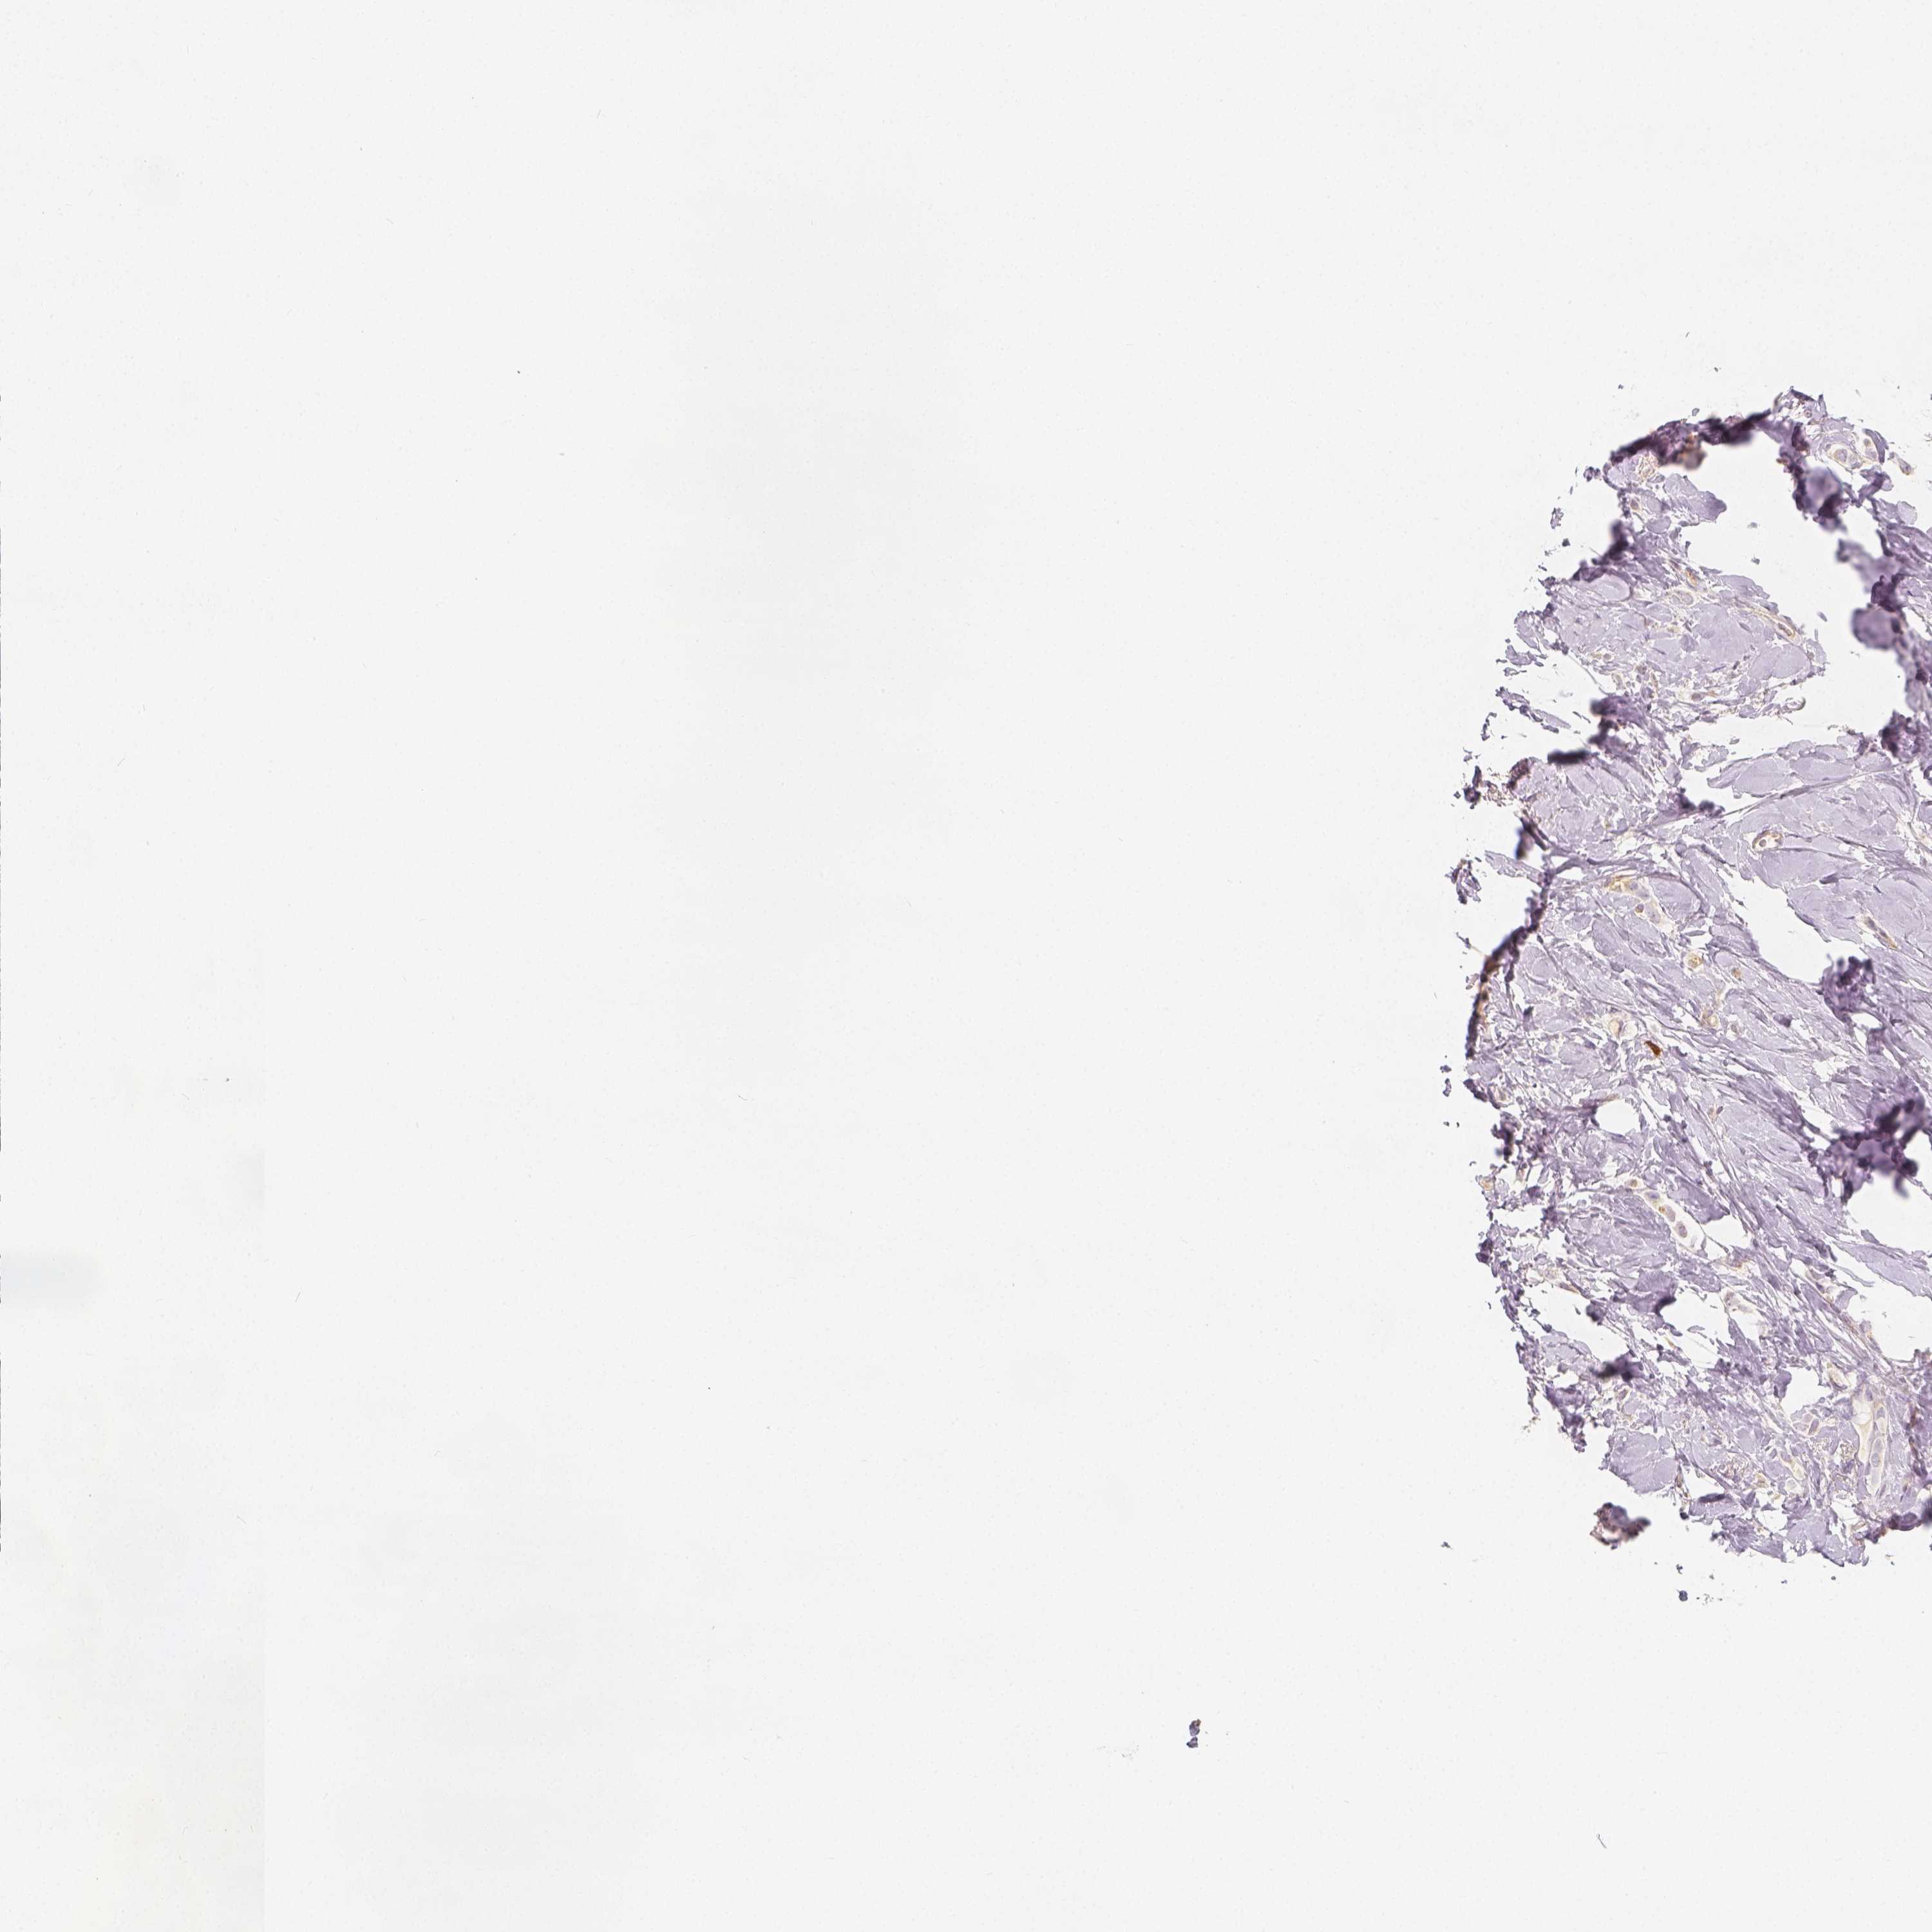

BRCA TCGA BRCA VALIDATION PROTEIN EXPRESSION